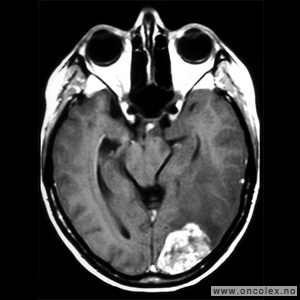

Vestibularisschwannom

Av hjernenervesvulstene er det vestibularisschwannom som er vanligst. Schwannomer kan forekomme på flere hjernenerver, men er i de fleste tilfeller altså lokalisert til balansedelen av hørsels- og balansenerven (åttende hjernenerve). Vestibularisschwannom diagnostiseres vanligvis i 40–50 års alder og er noe hyppigere hos kvinner enn hos menn. Nesten alle vestibularisschwannomer er godartede og vokser langsomt. Hos 5 % av pasientene finner man vestibularisschwannom på begge sider. Disse pasientene har per definisjon nevrofibromatose type 2.